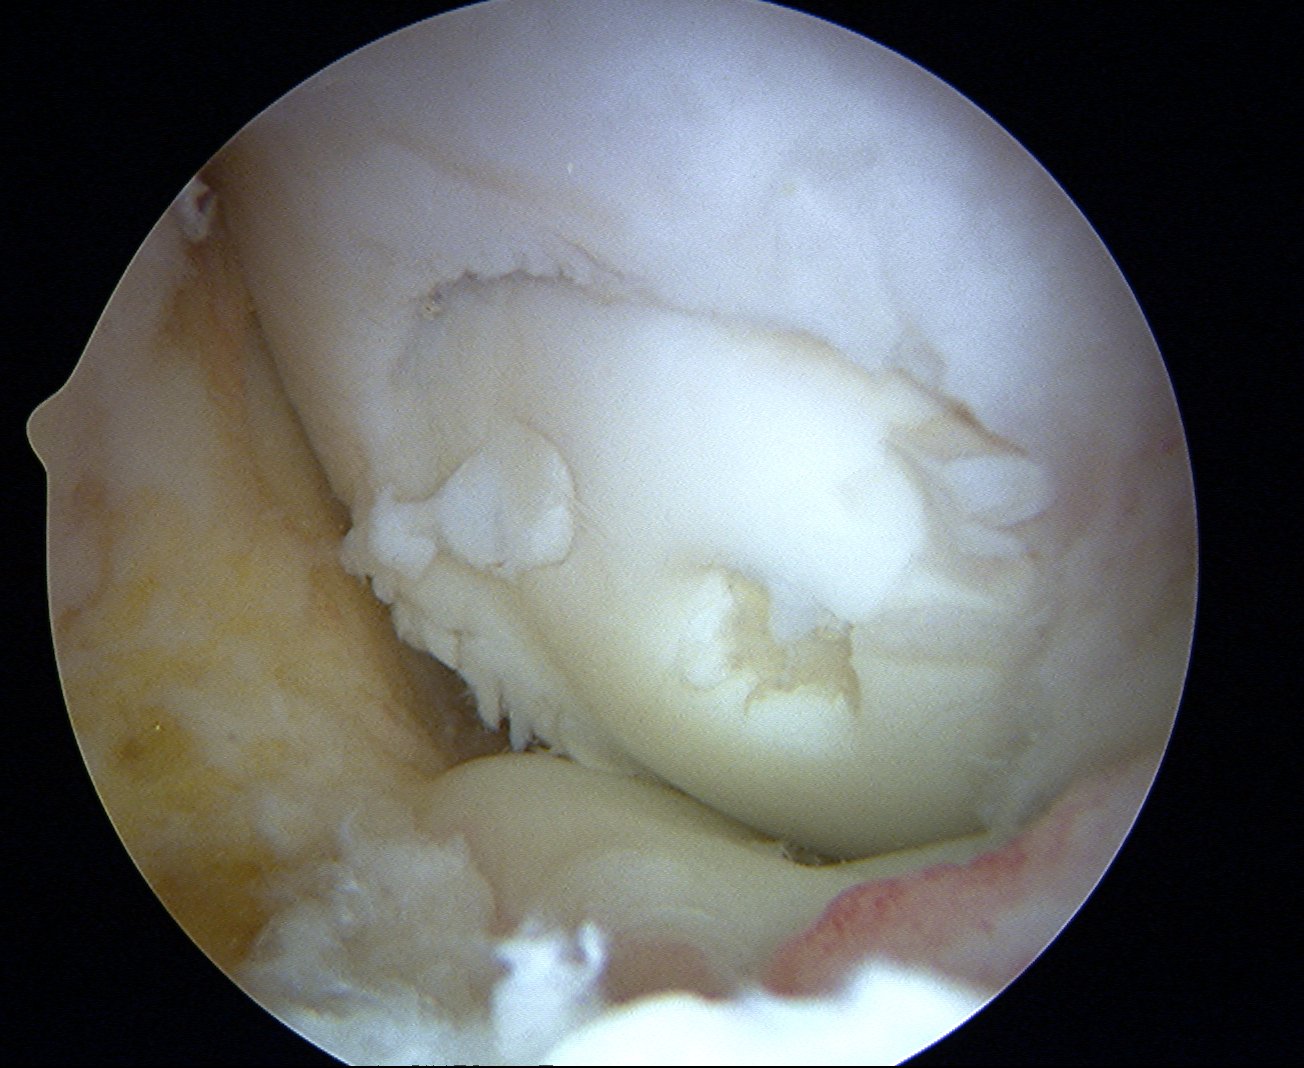

MFC unstable OCD

LFC unstable OCD

2. Unstable and salvageable lesions

- fluid behind lesion on MRI

- cartilage breach on arthroscopy